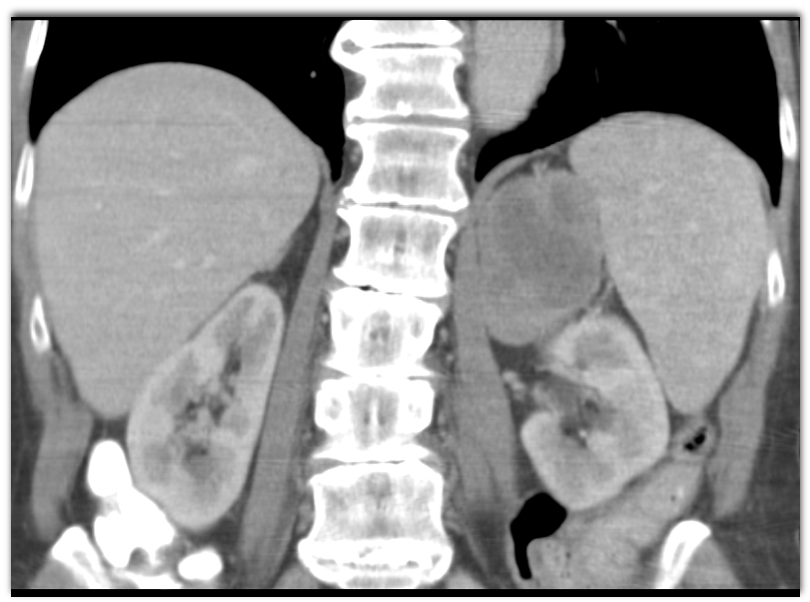

metastatic renal cell carcinoma

metastatic hepatoma

pulmonary artery sarcoma

lymphoma